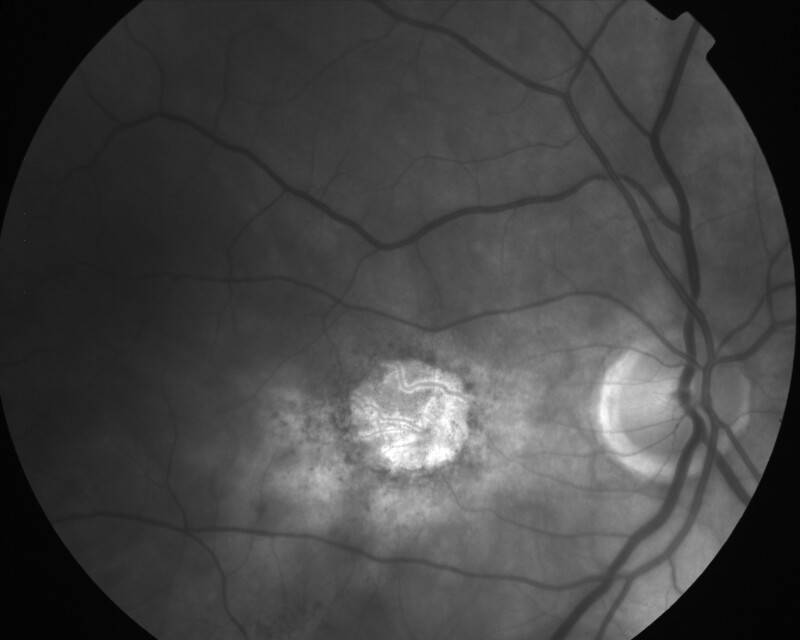

ATROPHIE AREOLAIRE CENTRALE

IMG0001.JPG